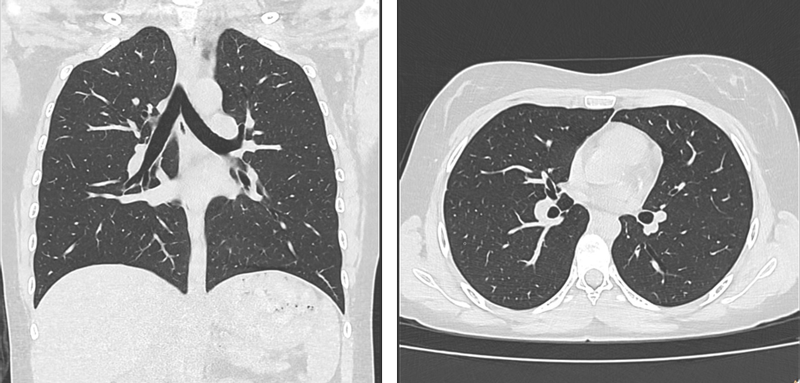

Thorax/Abdomen nativ, Pat adipös, CTDI 6,3, DLP 292

Aufgenommen mit einem Philips CT 5300, CTDIvol [mGy] = 0.7